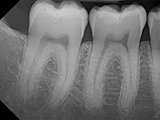

| X-Ray Example |

X-ray taken with the Dexis Sensor |

Dental X-Ray Comparison

X-ray taken with the Dexis™ sensorSchick